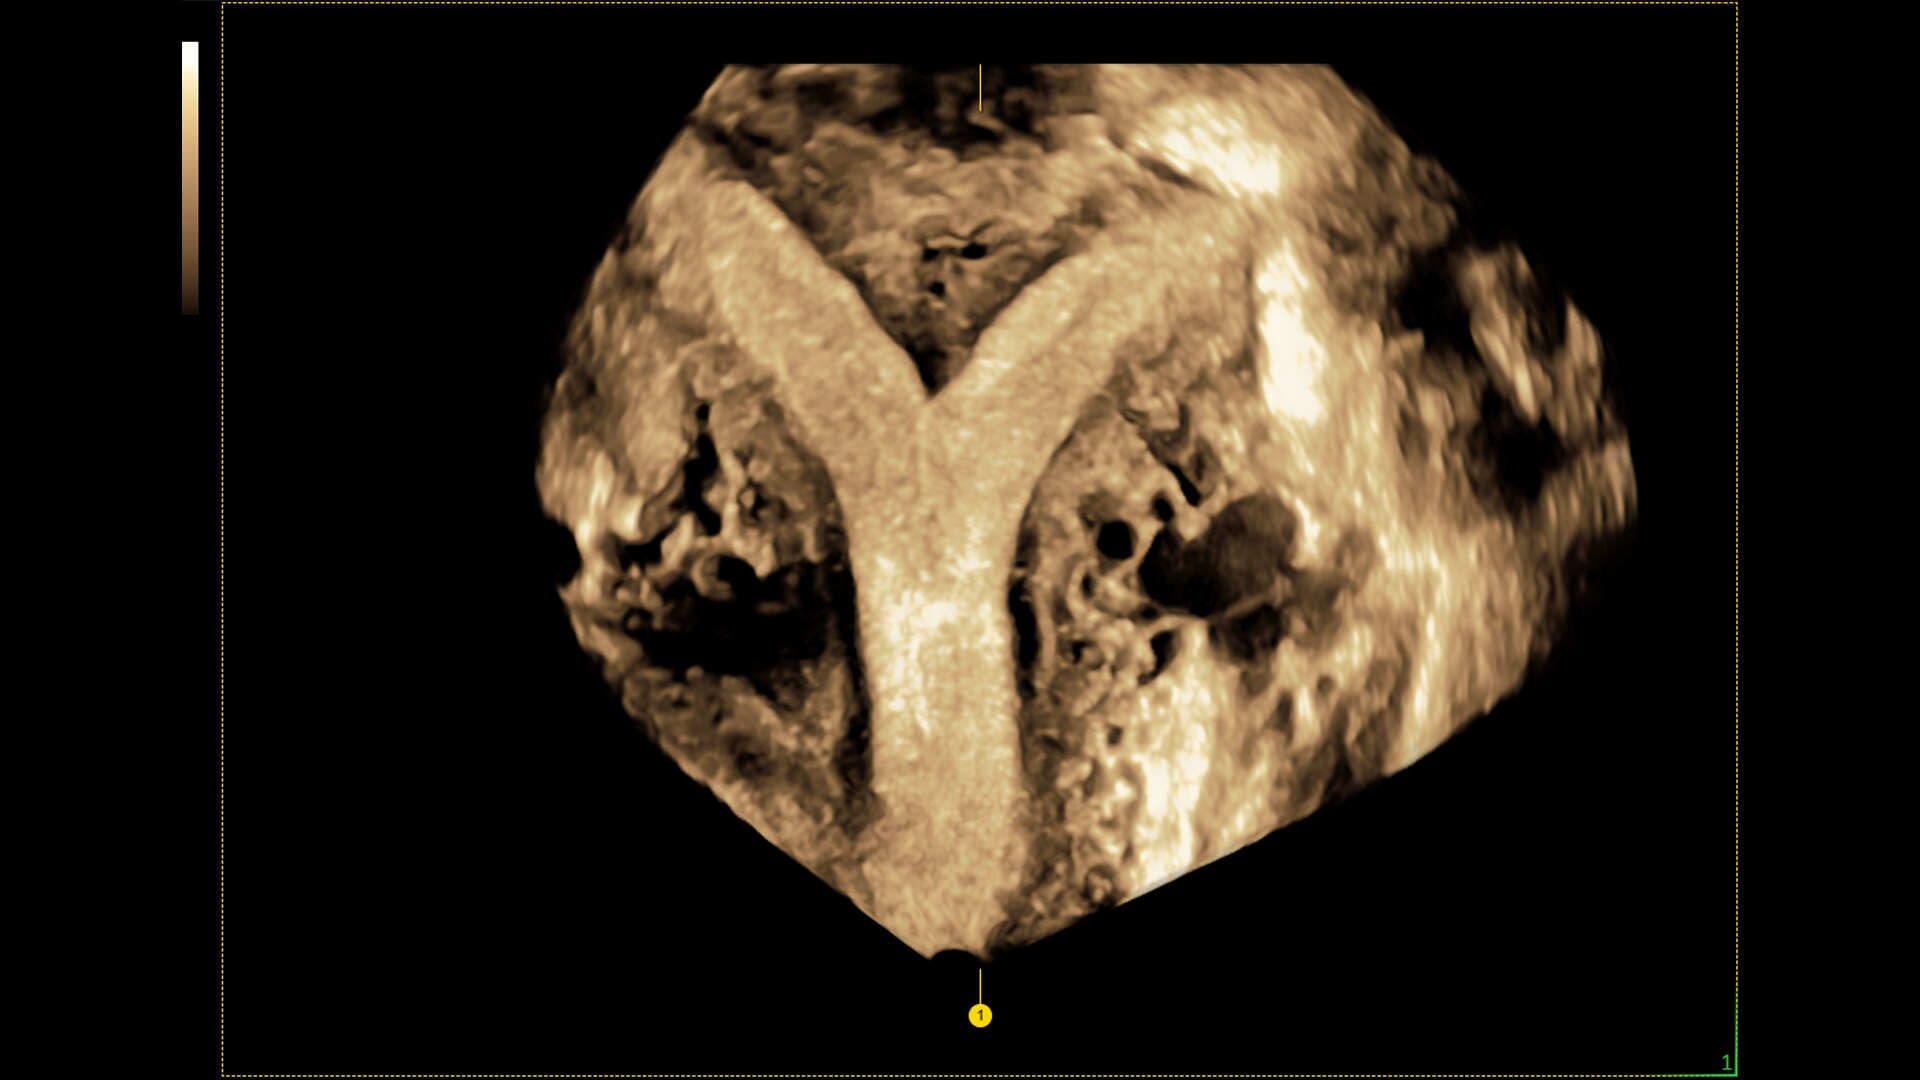

SonoGYN

Combines our Uterine Trace tool and Fibroid Mapping feature, an AI reporting tool that standardizes and streamlines fibroid documentation by mapping, measuring, and classifying fibroids in 3D.